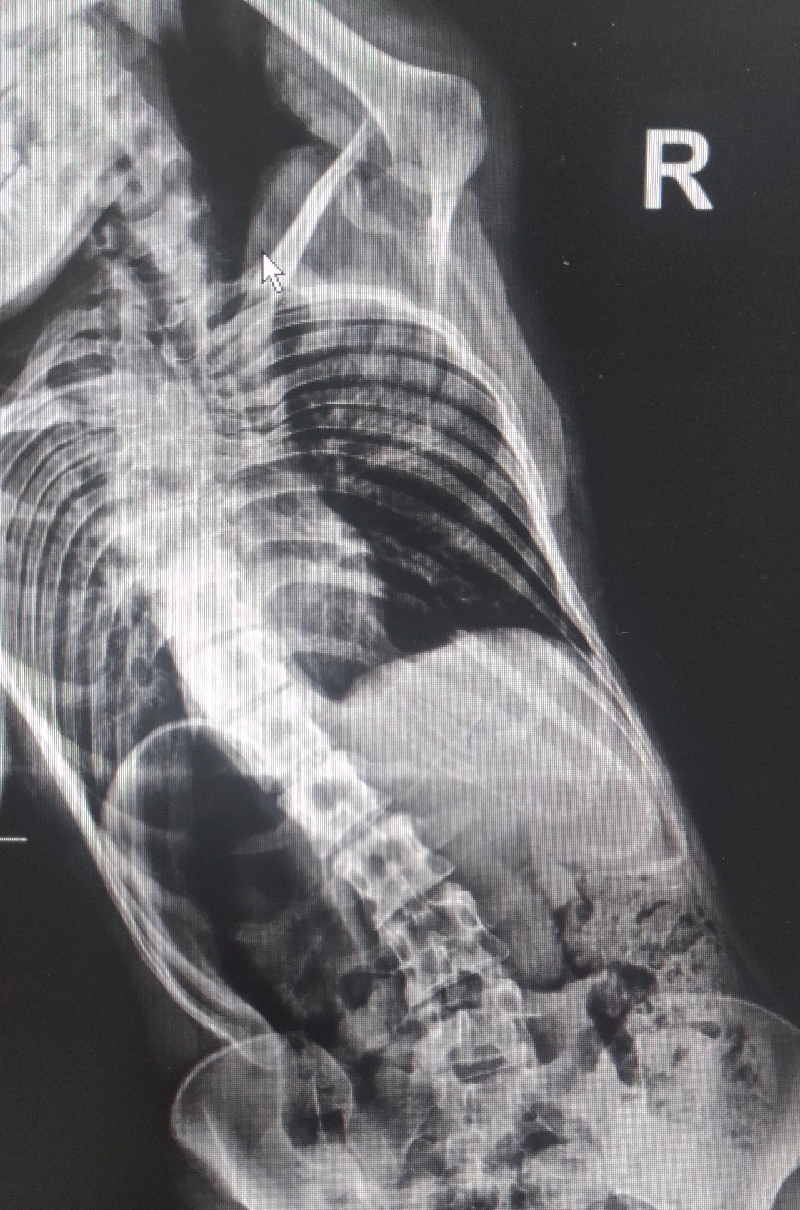

入院后,经检查,八年时间里,姗姗的脊柱侧凸畸形cobb角从10度已发展到50度。1月16号上午,陶惠人教授团队和西安大兴医院脊柱外科团队为姗姗实施了脊柱侧弯矫正手术。

“手术的难度在于,患者胸1到胸11椎体分节不全,畸形融合。”西安大兴医院脊柱外科袁斌主任介绍,椎体融合导致术中经后路松解时,难度比较大。另一个,辨认解剖结构比较困难,钉子需要打在椎弓根上,非常考验术者的水平和经验。

因此,在术前医生反复测量椎弓根长度和宽度,并通过术中CT确定钉子精准定位。手术中患者采用俯卧位,在全麻状态下手术,一名医生对患者进行神经电生理检测,随时监控脊髓安全,确保万无一失。整个手术历时4个半小时,从胸2到腰4共植入18颗钉子,手术很顺利。